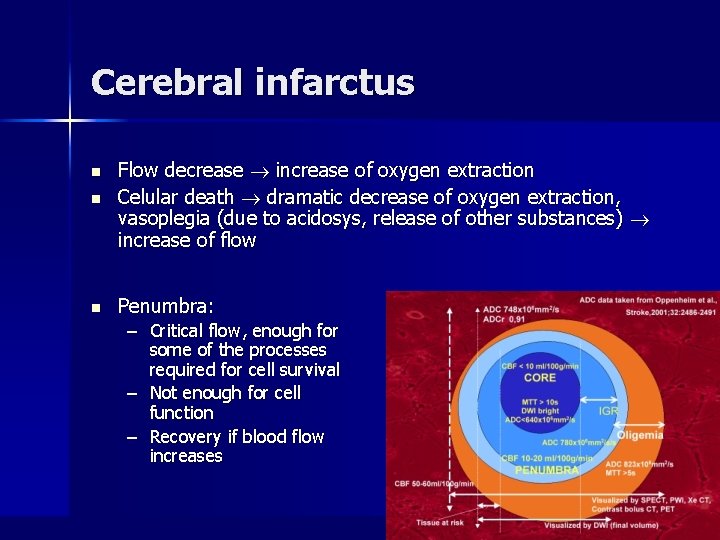

Cerebral infarctus n Flow decrease increase of oxygen extraction Celular death dramatic decrease of oxygen extraction, vasoplegia (due to acidosys, release of other substances) increase of flow n Penumbra: n – Critical flow, enough for some of the processes required for cell survival – Not enough for cell function – Recovery if blood flow increases